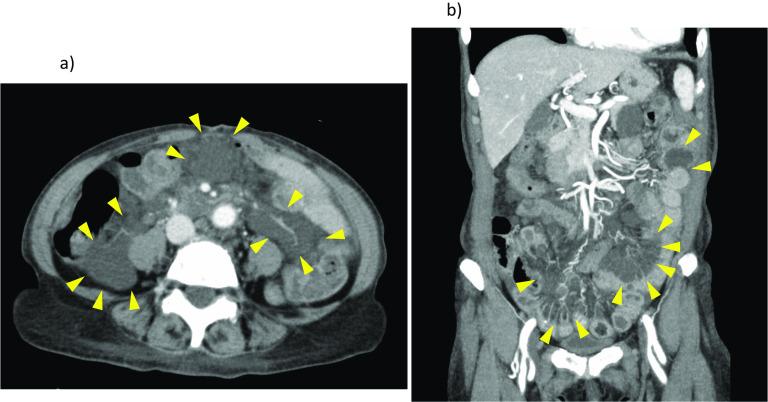

Herein, we describe an elderly Japanese woman with anemia, hypoalbuminemia, and episodic bleeding due to multiple intestinal lymphangiomas. Abdominal computed tomography revealed multiple low-density defects of mesentery, with areas of intermediate (T1 images) or high (T2 images) signal intensity similarly dispersed in magnetic resonance scanning sequences. Single-balloon enteroscopy was undertaken, enabling identification and tattooing of a small intestinal bleeding source. Laparoscopy-assisted resection at this site served to control related hemorrhage, removing a histologically confirmed hemolymphangioma. Having recovered uneventfully, the patient remained stable 2 months postoperatively.

在此,我们描述了一位患有贫血、低白蛋白血症且因多发肠道淋巴管瘤而出现间歇性出血的老年日本女性。腹部计算机断层扫描显示肠系膜有多个低密度缺损区,在磁共振扫描序列中,类似区域在T1图像上呈中等信号强度,在T2图像上呈高信号强度。进行了单气囊小肠镜检查,得以识别并标记小肠出血源。在此部位进行腹腔镜辅助切除术控制了相关出血,切除了经组织学证实的血管淋巴管瘤。患者恢复顺利,术后2个月保持稳定。